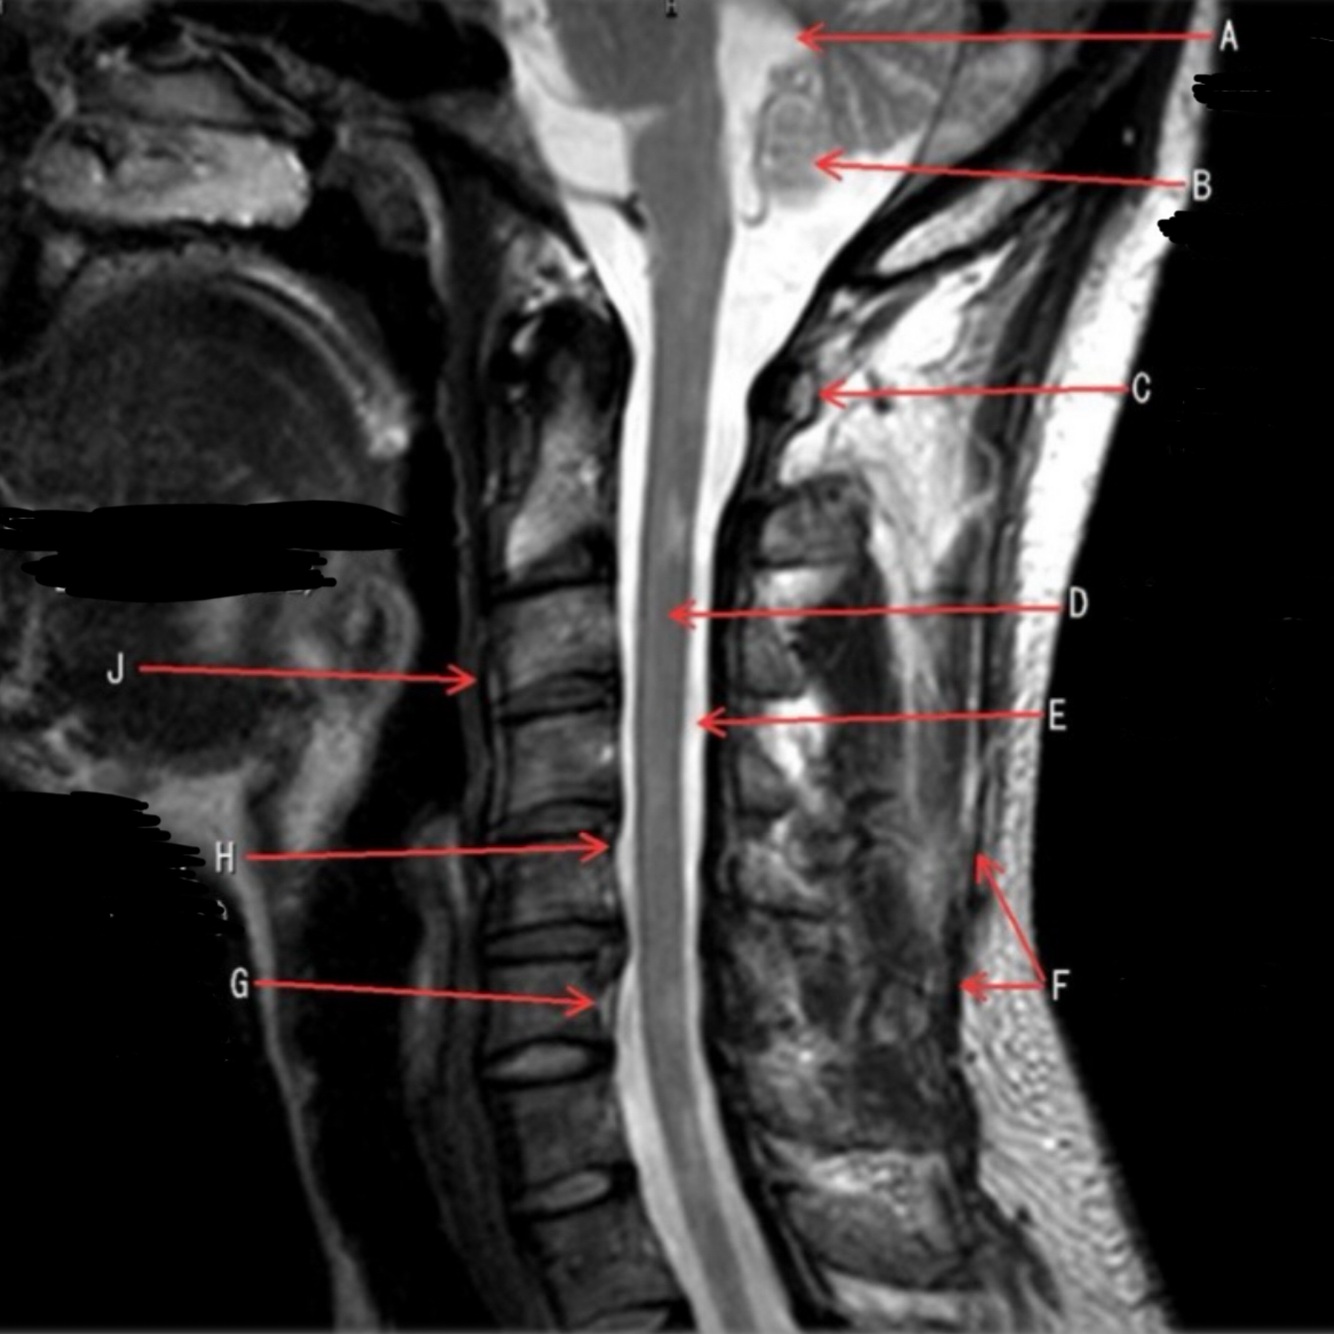

(65 cards)

1

What is letter A?

4TH VENTRICLE

2

What is letter B?

CEREBELLUM

3

What is letter C?

POSTERIOR ARCH OF C1

4

What is letter D?

SPINAL CORD

5

What is letter E?

CSF

6

What is letter F?

SPINOUS LIGAMENT

7

What is letter G?

VENUS PLEXUS

8

What is letter H?

POSTERIOR LONGITUDINAL LIGAMENT (PLL)

9

What is letter J?

ANTERIOR LONGITUDINAL LIGAMENT (ALL)